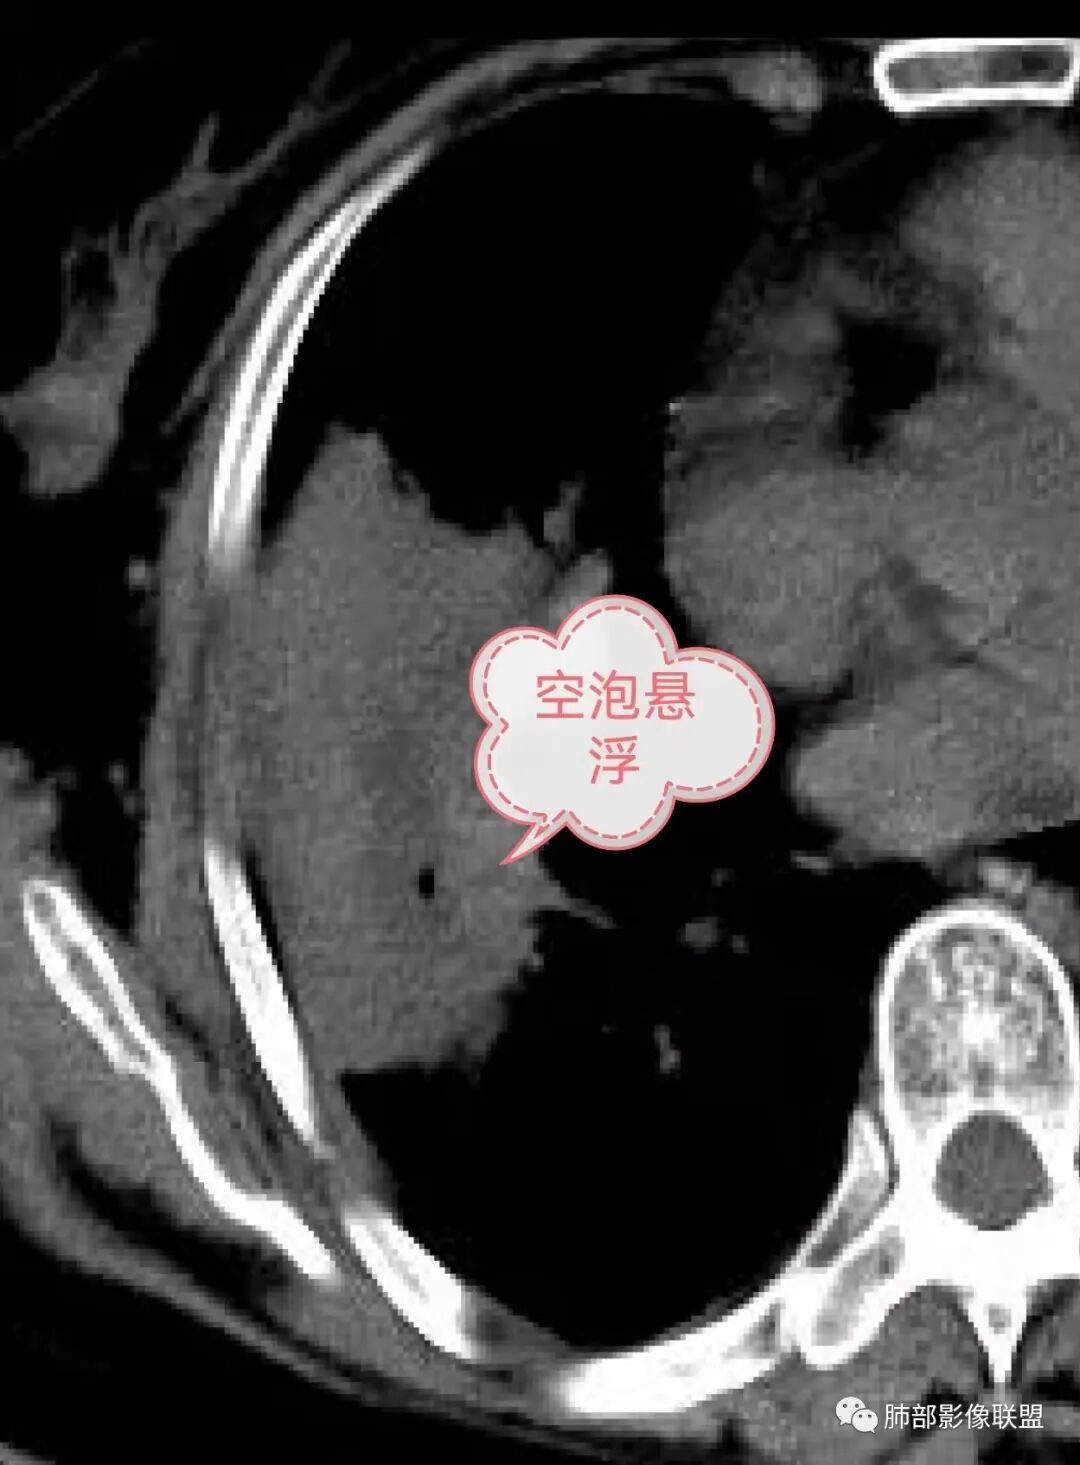

右肺中叶大片实变,内见大片的坏死,中叶外侧段支气管阻塞,相邻胸膜增厚,间隔约四个月后复查,发现低密度坏死内可见气泡影,老年人,反复迁延不愈的病变要考虑恶性,首先考虑腺癌伴感染。鉴别慢性脓肿。

气泡

老年女性,慢性病史,炎性指标稍高,肿标正常,右中下肺大片实变,跨叶生长,边界清,收缩力差,膨隆生长为主,支气管杵状截断,均匀强化,其内坏死边界清,可见悬浮气泡,整体观察,病灶膨隆生长为主,邻近肺野无播散灶,形态单一,尽管慢性病史,影像不支持OP和TB,支气管截断呈杵状,肿标正常,均匀强化,虽是高龄患者,诊断恶性肿瘤有点牵强,综和分析,首选炎性病变放线菌感染,其次考虑低度恶性占位炎机母。